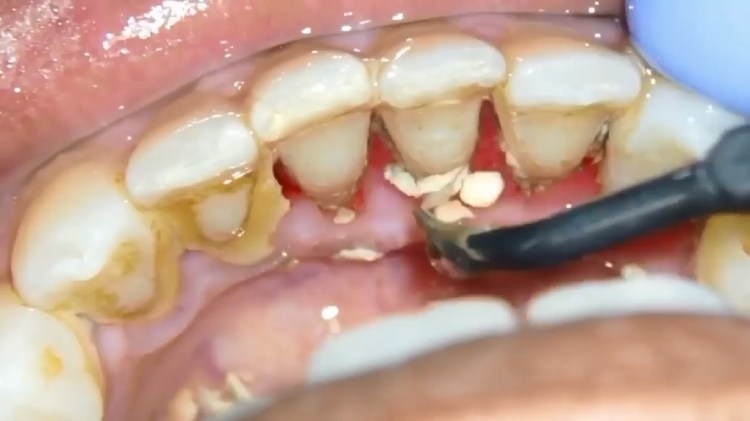

عملیات جرم گیری دندان نسبت به بسیاری از روش های دیگر با پیچیدگی هایی همراه است و بیمار نیازمند شناخت آن ها خواهد بود. حذف دقیق باکتری های پلاک روی سطح دندان به روشی اصولی، هدفی است که دندان پزشکان با جرم گیری دنبال می کنند و از مزایای جرم گیری دندان نیز هست. در صورت استفاده از روش دستی، دندان پزشک جرم گیری را با ابزار فلزی خود انجام می دهد. این قطعه بسیار نازک است و زیر لثه قرار می گیرد. در واقع بخش هایی که شاید بیمار دسترسی راحتی به آن ها نداشته باشد، توسط این روش برداشته می شود.

جدا از آن، استفاده از شیوه دستگاهی با استفاده از ابزار اولتراسونیک صورت می گیرد. این دستگاه شامل یک نوک فلزی ارتعاشی با اسپری آب خنک است تا چنین عملیاتی به صورت کامل تمام شود. این روش با نام روت پلنینگ هم شناخته می شود که برای رسیدگی و تمیز کردن ریشه های عمیق دندان ها است. این روش در واقع همان پوسته پوسته شدن است که سطح ریشه را کاملا صاف کرده تا لثه ها به یکدیگر بچسبند.